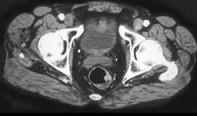

问题 男性,41岁,血便,肛诊触及左侧直肠壁一质硬小结节,结合CT所见应考虑为 ( )

选项 A.直肠腺瘤 B.直肠癌 C.直肠息肉 D.直肠转移瘤 E.直肠间质瘤

答案 B